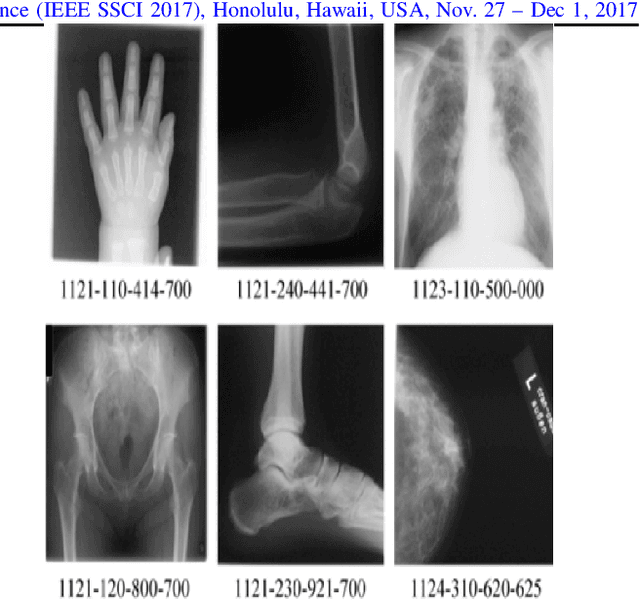

Abstract:Content-based image retrieval (CBIR) of medical images in large datasets to identify similar images when a query image is given can be very useful in improving the diagnostic decision of the clinical experts and as well in educational scenarios. In this paper, we used two stage classification and retrieval approach to retrieve similar images. First, the Gabor filters are applied to Radon-transformed images to extract features and to train a multi-class SVM. Then based on the classification results and using an extracted Gabor barcode, similar images are retrieved. The proposed method was tested on IRMA dataset which contains more than 14,000 images. Experimental results show the efficiency of our approach in retrieving similar images compared to other Gabor-Radon-oriented methods.